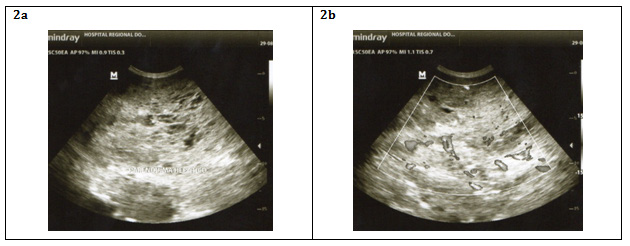

CT with dynamic contrast (arterial, portal and late venous phases) is preferred before routine CT scan. It observes contrast enhancement around the edges of the tumor in the initial arterial phase, centripetal contrast improves in the portal phase and in the late venous phase, the contrast distributes uniformly throughout the tumor. However, when there is an intratumoral hemorrhage or areas of necrosis as in the HHG the hemangioma becomes a heterogeneous mass with high density inside it11 (Figure 3).

Figure 3 A: Hepatomegaly to predominance of the left hepatic lobe with multiple hypodense solid nodules, which tend to converge with each other throughout the hepatic parenchyma displacing caudal to other intra-abdominal organs.

B: After administration of contrast is evident a peripheral enhancement of the nodules in centripetal shape.

C: In the late phase the pattern of progressive centripetal filling is confirmed, as well as necrosis and calcification characteristics.

Photos from the Department of Radiology, “Hospital Regional Docente de Enfermedades Neoplásicas”